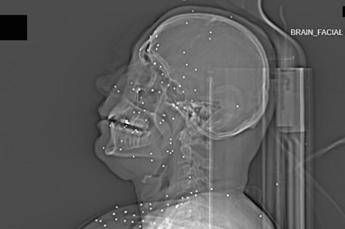

Il volto di Anahita – nome di fantasia, poco più che ventenne – appare come un cielo notturno attraversato da punti luminosi. Piccole sfere metalliche, da 2 a 5 millimetri, disseminate sul viso, nelle orbite oculari, persino nella massa scura del cervello. Sono proiettili “birdshot”, pallini da caccia sparati da un fucile a pompa. A distanza ravvicinata, spiegano gli esperti, non sono affatto “meno letali”: possono frantumare ossa, devastare tessuti molli, perforare facilmente un bulbo oculare. Anahita ha perso almeno un occhio, forse entrambi.

Quell’immagine non è un caso isolato. Fa parte di oltre 75 set di esami diagnostici provenienti da un singolo ospedale di una grande città iraniana, raccolti nel corso di una sola serata, durante la stretta repressiva di gennaio. Una concentrazione temporale che, già di per sé, racconta una dinamica da “mass casualty”, evento con numerose vittime simultanee, tipico degli scenari di guerra o dei grandi disastri.

Le scansioni mostrano ferite che i medici definiscono “catastrofiche”. Vahid – altro nome modificato – presenta un proiettile di grosso calibro conficcato nel collo. La trachea è spinta lateralmente, il sangue si accumula, i tessuti gonfi e danneggiati comprimono le strutture vitali. In un altro caso, un uomo di mezza età ha un proiettile sospeso nel cervello, accompagnato da una bolla di gas intracranica: segno di trauma devastante, al quale verosimilmente non si può sopravvivere. Due giovani uomini mostrano pallottole ad alto calibro alloggiate accanto alla colonna vertebrale. Una giovane donna presenta un proiettile deformato che sembra aver attraversato la gabbia toracica, lesionato il polmone e arrestato la sua corsa vicino alla spina dorsale.

Le valutazioni, condotte congiuntamente dal Guardian e dalla piattaforma di fact-checking Factnameh, sono state affidate a un panel indipendente di specialisti internazionali: medici d’urgenza, radiologi, esperti di trauma imaging e balistica. Un ex medico iraniano di pronto soccorso, anch’egli consultato, ha confermato la coerenza del software utilizzato per gli esami e l’assenza di segni di manomissione. Gli esperti precisano che, senza cartelle cliniche complete, non è possibile formulare diagnosi definitive sui singoli pazienti. Ma il quadro complessivo, spiegano, è inequivocabile.

“Se spari con armi di quel tipo contro delle persone, stai cercando di ucciderle.” La frase di uno degli specialisti di imaging traumatico riassume la sostanza tecnica dell’inchiesta. Le immagini mostrano proiettili full metal jacket, tipicamente utilizzati nei fucili d’assalto come AK-47 o KL-133, armi in dotazione ai Pasdaran, il Corpo delle guardie rivoluzionarie islamiche (IRGC). Non strumenti di controllo della folla, ma armamenti progettati per la guerra.

Accanto ai colpi di grosso calibro, emerge con forza un altro elemento: l’uso sistematico dei pallini metallici. L’Iran è tra i pochi Paesi in cui le forze di sicurezza impiegano birdshot metallico. A lunga distanza, i pallini si disperdono e colpiscono indiscriminatamente. A distanza ravvicinata, diventano devastanti: decine, talvolta centinaia di micro-proiettili che penetrano simultaneamente nei tessuti.

Le radiografie raccontano questa brutalità in modo quasi didascalico. Il torace di Ali – anche qui, nome di fantasia – contiene oltre 174 pallini metallici concentrati nella cavità destra. Il polmone parzialmente collassato, circondato da sangue e gas. Secondo gli esperti consultati, anche con un intervento chirurgico immediato e massiccio, il rischio di morte rimane altissimo.